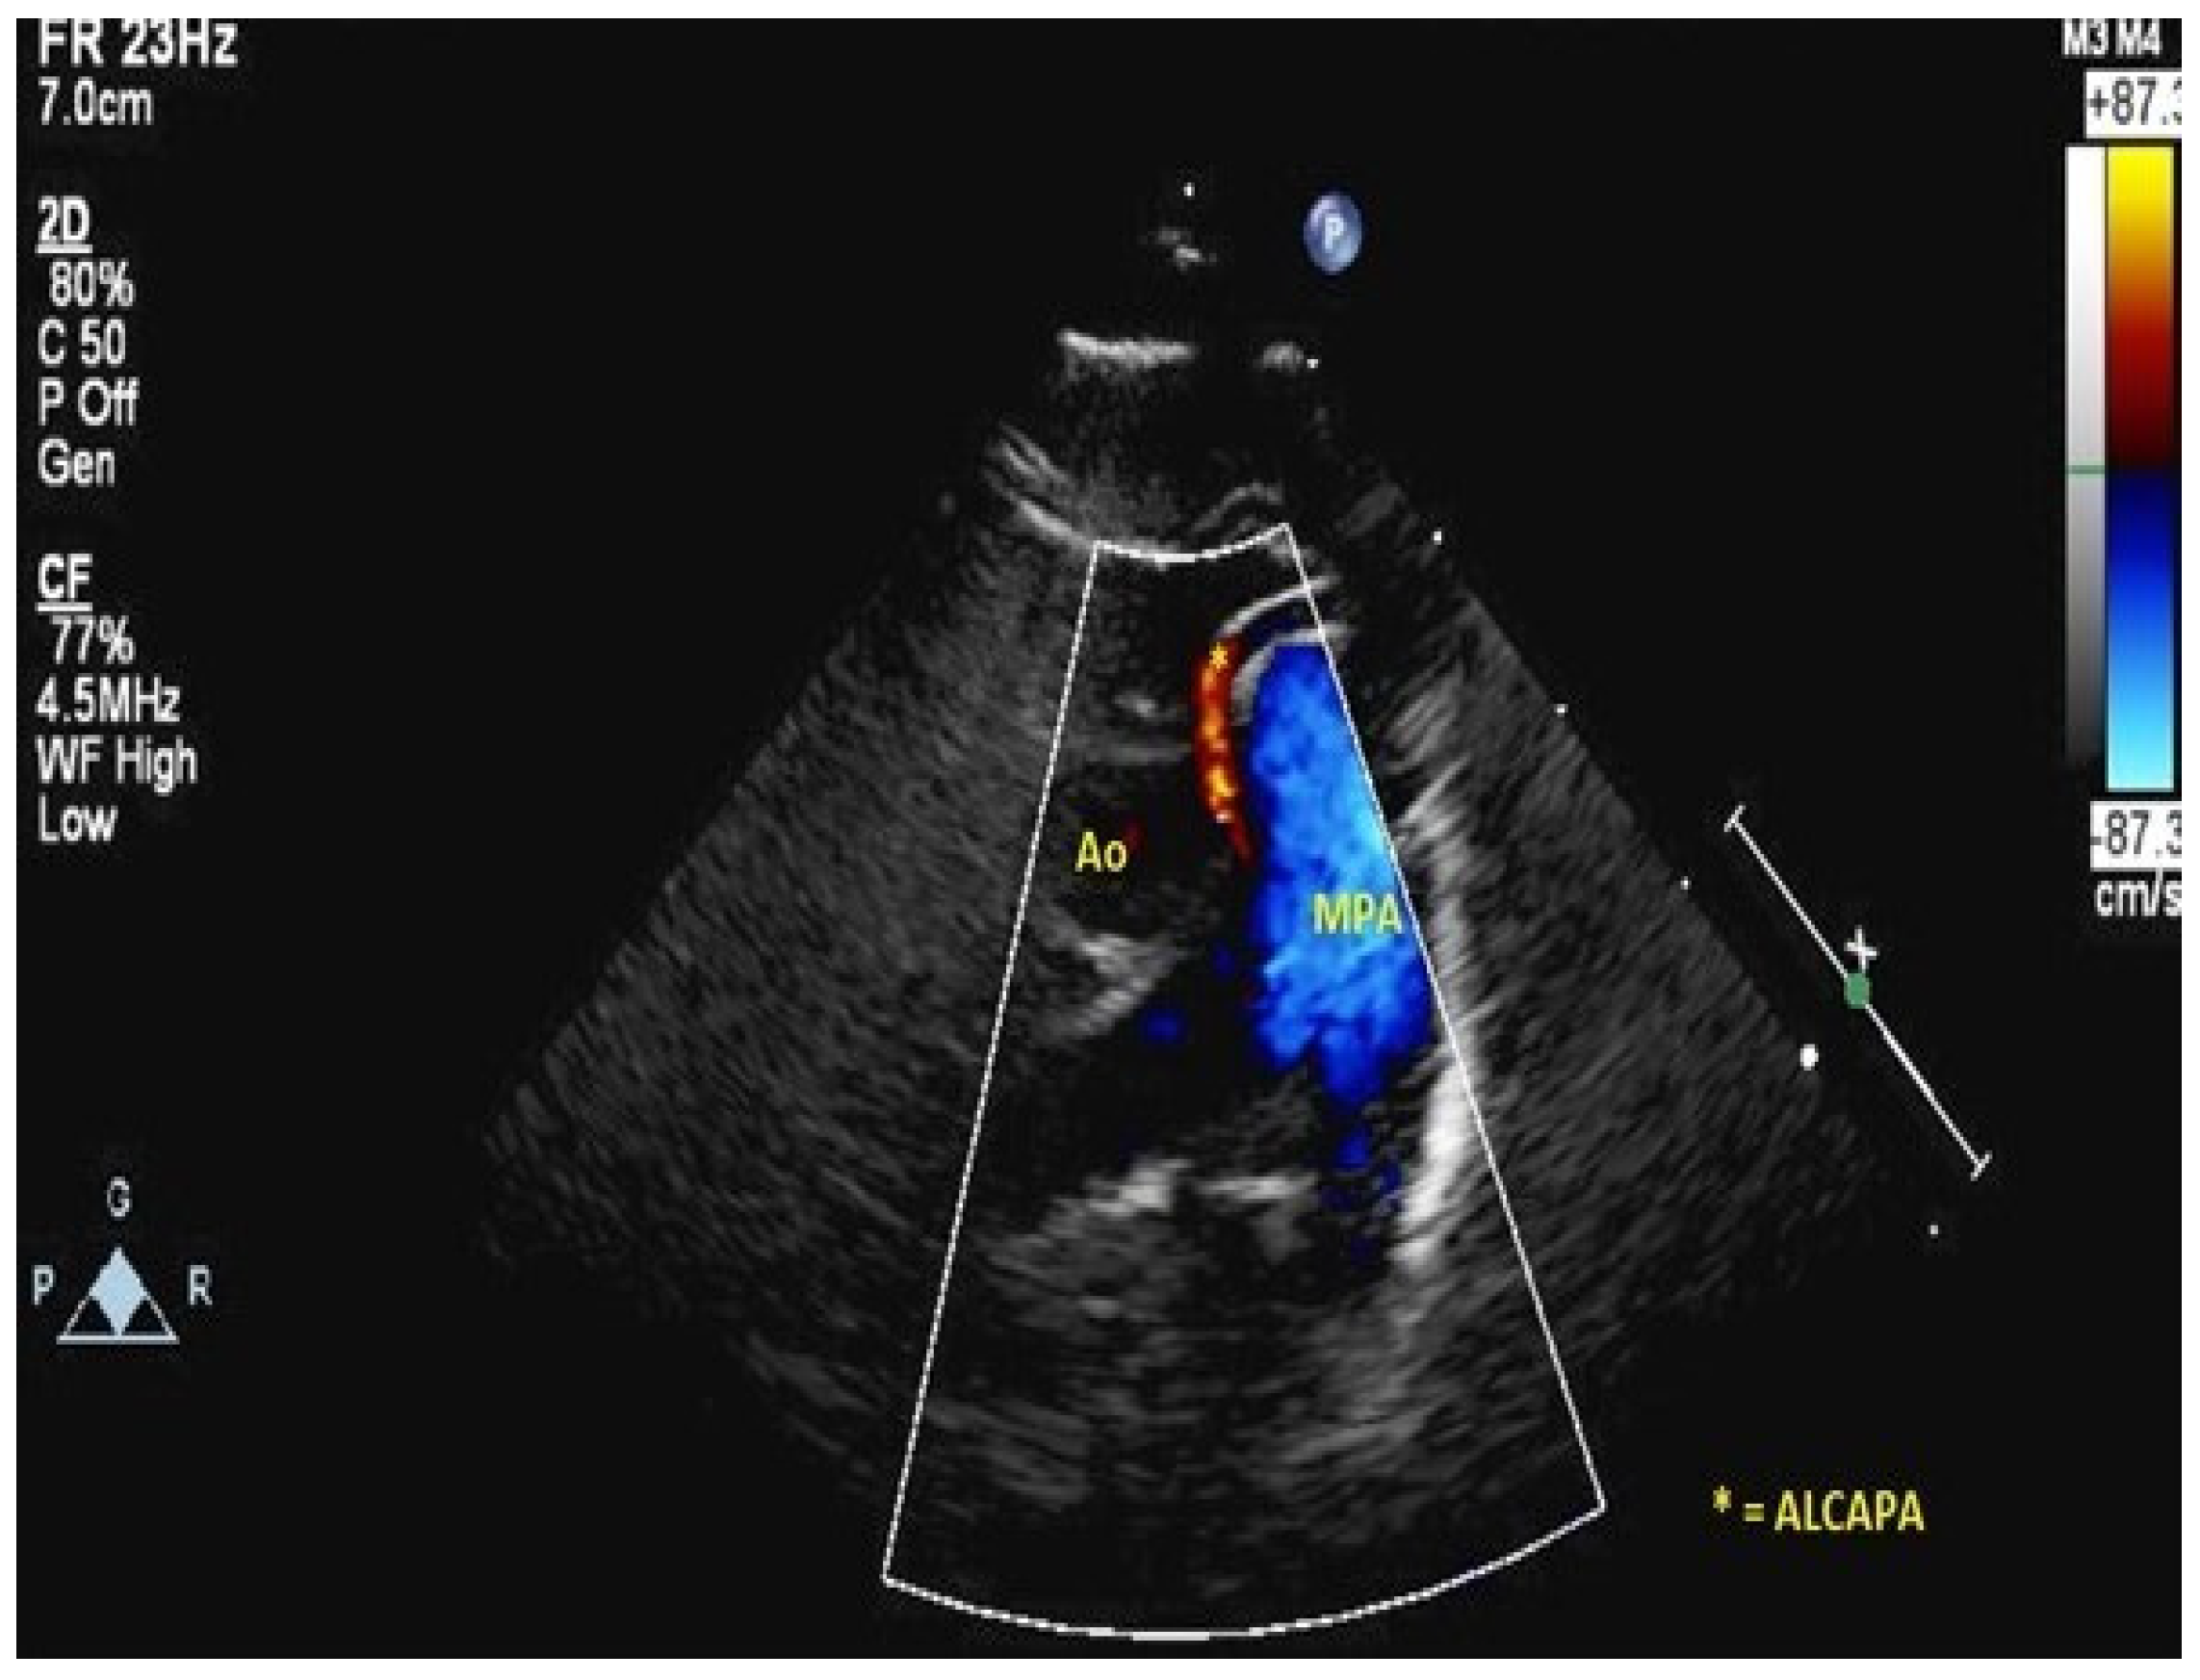

- Peña, E.; Nguyen, E.T.; Merchant, N.; Dennie, C. ALCAPA syndrome: Not just a pediatric disease. Radiographics 2009, 29, 553–565. [Google Scholar] [CrossRef]